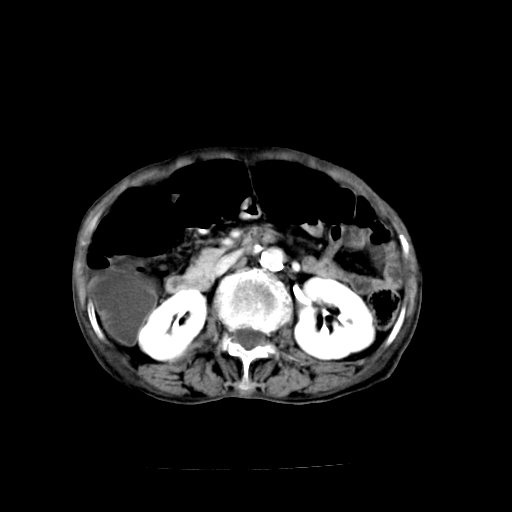

1)不排除胃窦癌;建议行胃镜检查。 2)局灶性脂肪肝。腹水。

考虑:胃窦ca,腹水,脂肪肝

支持考虑1、胃窦癌?建议行胃镜!; 2、局灶性脂肪肝。  3、双侧胸腔积液,胸膜增厚